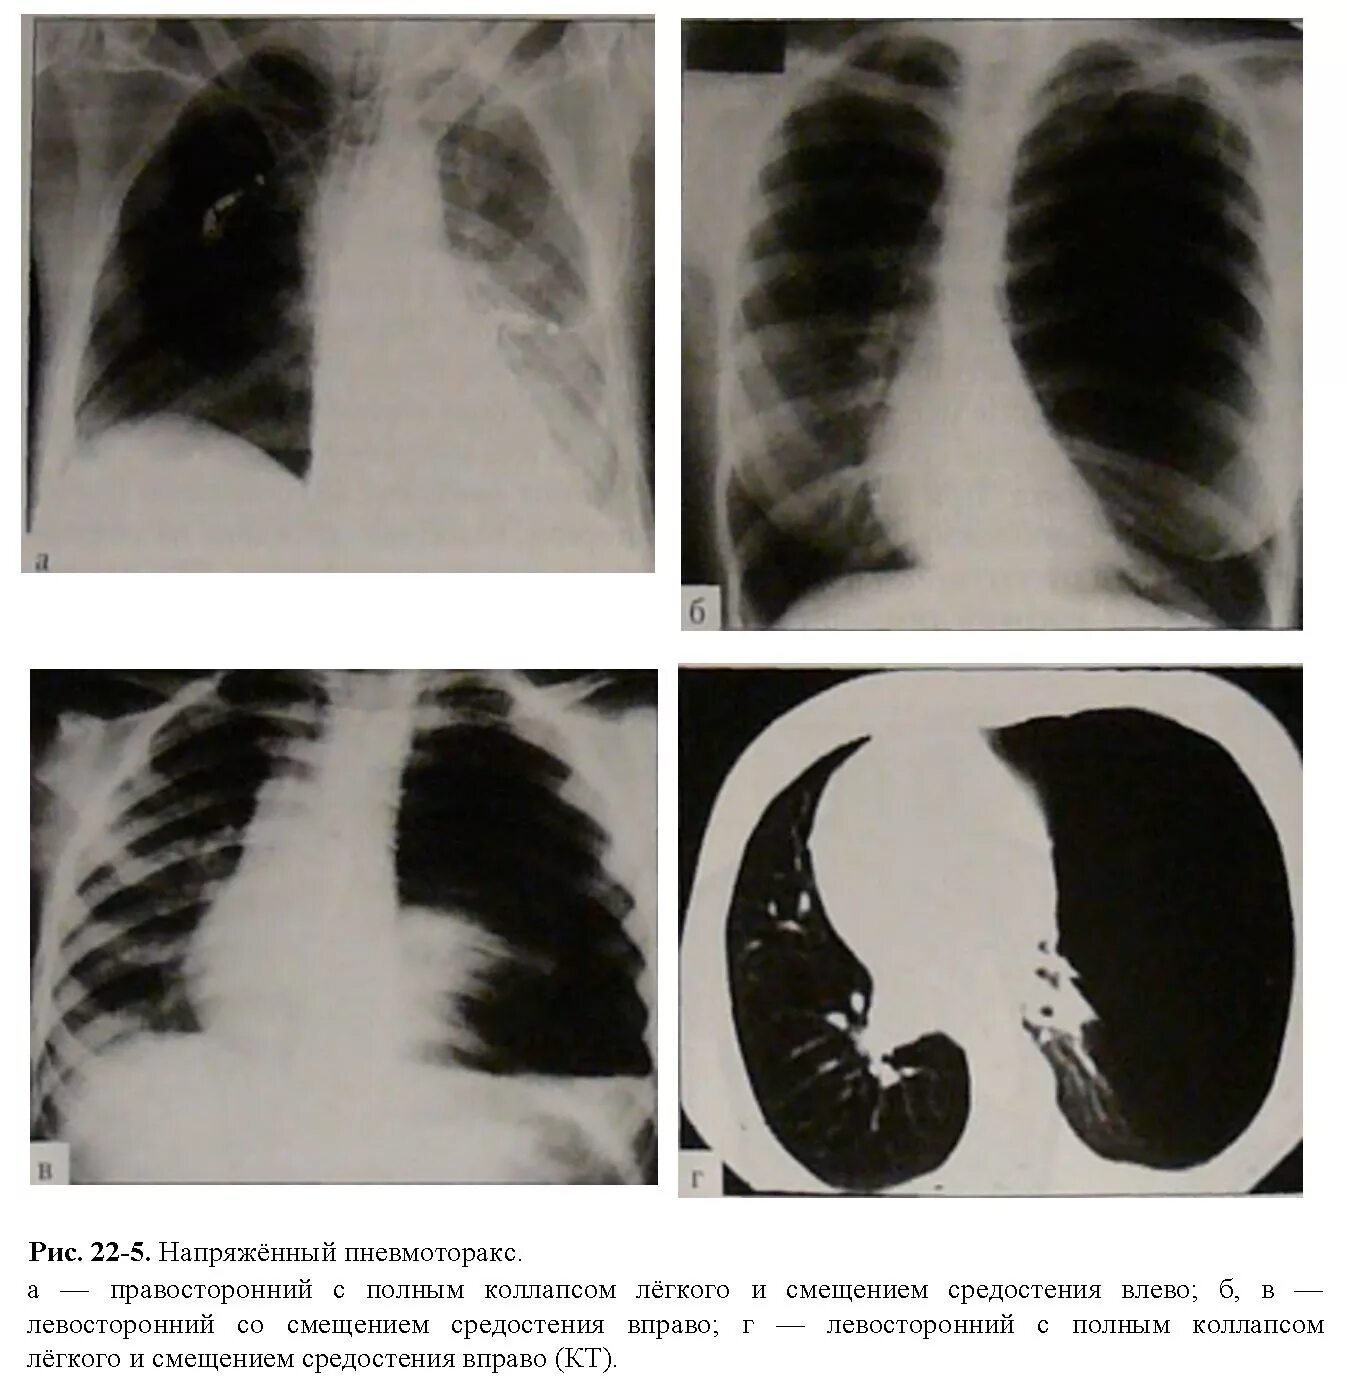

Коллабированное легкое при пневмотораксе